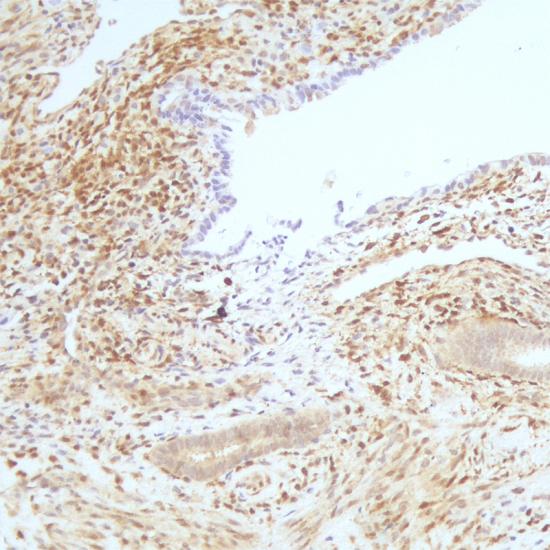

PTEN抗體試劑(免疫組織化學(xué)) 閩廈械備20180201號

• 陽性部位:

細胞漿/細胞核

• 陽性對照:

子宮內(nèi)膜癌

PTEN也稱MMAC1或TEP1,是一種腫瘤抑制基因,定位于人染色體10q23。該基因編碼的磷酸酶可調(diào)節(jié)細胞周期、凋亡的進程。研究發(fā)現(xiàn),在人類多種腫瘤和遺傳性腫瘤易感綜合癥疾病中存在 PTEN的缺失和突變,在膠質(zhì)瘤、乳腺癌及前列腺癌中PTEN的表達與病人預(yù)后有一定相關(guān)性。